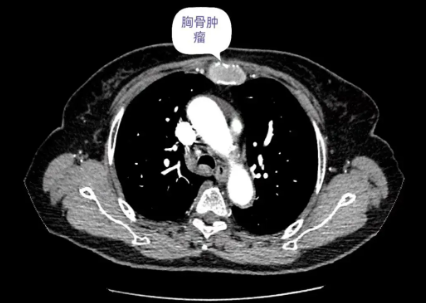

69岁女性患者,因“反复胸疼5月余”入院,查体胸骨区有压痛,入院后完善相关检查,行胸部CT提示:胸骨肿瘤,完善术前检查,行肿瘤切除+胸壁重建术,目前患者已康复出院。

▲胸壁三维重建(橙色区域为胸骨肿瘤)